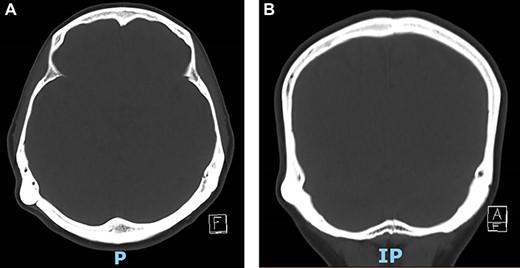

Non-contrast CT scan of the skull (Fig. 2) reported an outer table right retromastoid exophytic osseous mass, measuring 1.7 cm at its base. No destructive skull lesion and no intracranial extension were reported.

Computed tomography (CT) of temporal bone showing retro-mastoid osteoma in axial and coronal plane.